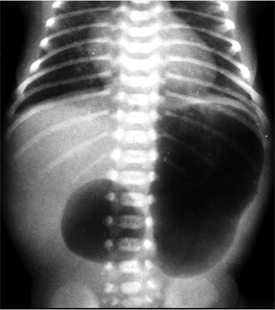

On the second day of life, there was a persistent vomiting even with an open gastric tube and the baby was submitted to a radiologic procedure that showed an enlarging of the gastric image and a second at the duodenum site, strongly suggesting a double bobble image of CDO (Figure 1).

Figure 1. Showed an enlarging of the gastric image and a second one at the duodenum site, strongly suggesting a double-bobble image of CDO.